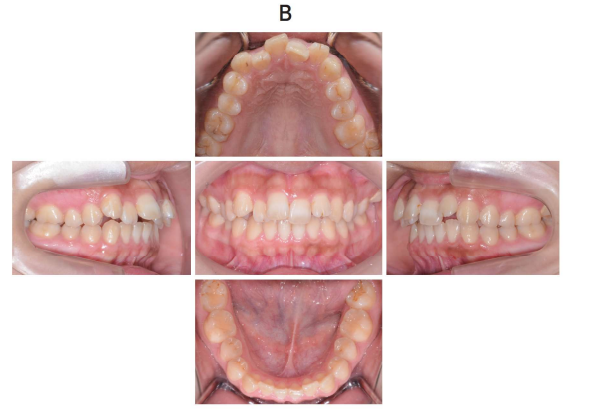

118回 A-77

22 歳の女性。上顎の歯並びが悪いことを主訴として来院した。診断の結果、抜歯を伴うマルチブラケット装置を用いた矯正歯科治療を行うこととした。初診時の顔面写真(別冊No. 25A)、口腔内写真(別冊No. 25B)及びエックス線画像(別冊No. 25C)を別に示す。セファロ分析の結果を図に示す。

解答:b

解説:

セファロ:下顎骨小さめ、上顎中切歯唇側傾斜

叢生:上顎 目立つ、下顎 スペースなさそうだが叢生ではない

臼歯関係:両側Ⅱ級

叢生具合から上顎のみの抜歯でよさそう。4番か5番で悩む。

5番を抜歯すると、前歯部の叢生を改善するのに時間がかかり、奥歯も移動するので更にⅡ級がひどくなると予想。なので4番を抜歯。